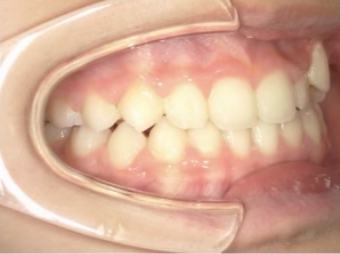

治療中④ 小4:10y1m

左上3が八重歯で萌出中